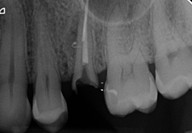

► Otturazione tridimensionale del sistema endodontico: tecniche di chiusura con guttapercha permoplasticizzata e chiusura con cementi bioceramici

Galleria fotografica